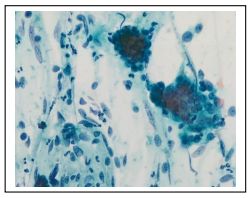

106. A 55-year-old woman with hematuria, urine cytology: What is the most likely diagnosis?

(A) CMV inclusion (B)Malakoplakia (C)Urothelial carcinoma, low grade (D)Adenocarcinoma